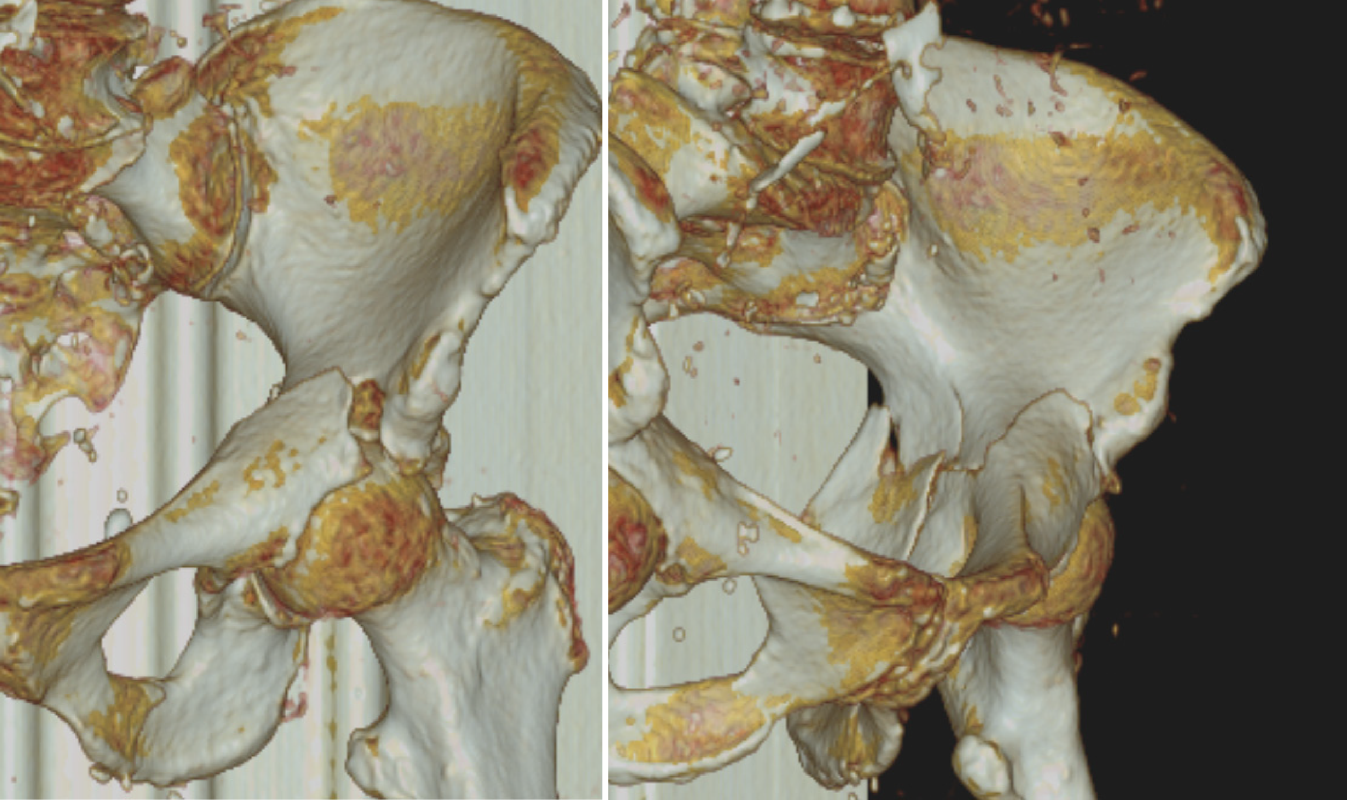

Abb. 2

In der präoperativen CT-Diagnostik kann die genaue Frakturmorphologie festgestellt und mögliche Therapieoptionen können eruiert werden. In der Rekonstruktion stellt sich die leicht dislozierte T‑Fraktur des Azetabulums Typ 6 nach Letournel und Judet dar